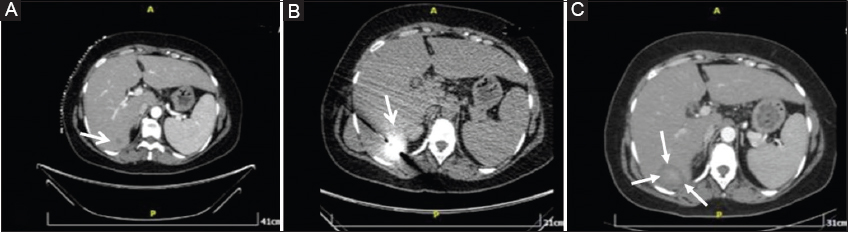

Figure 1 A 45-year-old woman with breast cancer and a single metastatic lesion in the liver, treated by percutaneous microwave ablation (pulsed mode). (A) Computed tomography (CT) image in the axial plane shows the lesion (arrow) in segment VI of the liver. (B) CT image in the axial plane shows the microwave antenna (arrow) in the final position. (C) CT image in the axial plane shows the ablation zone (arrows) immediately post ablation

MW ablation was always performed in an inpatient setting. Computed tomographic (CT) guidance with sequential scanning (120 Kv peak, 240 mAs wavelength and 2 mm slice thickness) was used for planning, targeting and intraprocedural modification during the ablation session. The analgesia protocol was the same throughout the cohort: 30 min prior to ablation tramadol was injected intravenously, diluted in 100 mL normal saline, whilst acetaminophen was administered during the ablation session to treat intraprocedural pain (amounts of both analgesics were based on each patient’s weight) [13]. Under local sterility, MW ablation was performed via a percutaneous approach in all cases. After the initial CT scan, a skin entry point was selected. All treatments were performed using the same MW ablation equipment (HS AMICA, HS Hospital Service SpA, Rome, Italy), comprising a 2450 MHz solid-state generator with integrated peristaltic pump (AMICA-GEN) and internally cooled MW applicators (AMICA-PROBE). The MW probe was inserted in the lesion of interest through sequential CT scans (Fig. 1). In all cases included in the present study ablation was performed using a single MW antenna. Once in the correct location, the ablation session was set up and performed according to a specific treatment plan, mainly stemming from a review of the coagulation charts provided by the manufacturer in consideration of the tumor size and location and the desired safety margin. These charts, based on lab experiments on ex vivo bovine liver, provide for the ablation dimensions (L × D) to be expected—with all the inherent limitations of an ex vivo animal model—for given settings of the energy delivery scheme (either continuous or pulsed, with tON=4 sec and tOFF=6 sec), the output power (up to 100 W in continuous mode and up to 140 W in pulsed mode) and the overall treatment time (up to 15 min). Depending on the size of the lesion to be treated, the ablation protocols in the CM group provided for 40 or 60 W for either 5 or 10 min, while in the PM group all sessions lasted 10 min at either 100 or 120 W. In either trial arm, whenever deemed necessary, the MW antenna was repositioned and a second ablation session was performed, so as to ensure that the final ablation completely encompassed both the target tumor and an annular safety zone around it at least 5 mm thick.

CT (contrast enhanced, in the arterial and portal venous phase of enhancement) was used to assess both the ablation zone size and the potential immediate complications at the end of the ablation treatment (Fig. 2). Exactly 30 min after the completion of ablation sessions, all patients completed a questionnaire in which they assigned a numeric pain intensity score from 0 (no pain) to 10. Patients were kept under observation for 24 h and eventually discharged. We evaluated technical success, complication rates and intraoperative pain scores. Pain score was evaluated using a brief pain inventory containing questions about pain intensity; answers were provided in terms of NVS [14]. Technical success was defined as complete coverage of the lesion by the ablation zone immediately after the procedure, plus a safety margin of at least 5 mm (as depicted by CT scan before and after iodinated contrast medium injection in the arterial and portal venous phases of enhancement). Complications were defined according to the Cardiovascular and Interventional Radiological Society of Europe (CIRSE) classification system [15].